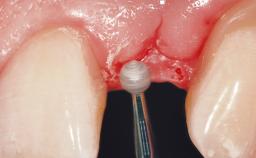

Bone Augmentation Horizontal|Simultaneous

Augmentation Materials Synthetic

Bone Volume Deficient horizontally, allowing simultaneous augumentation